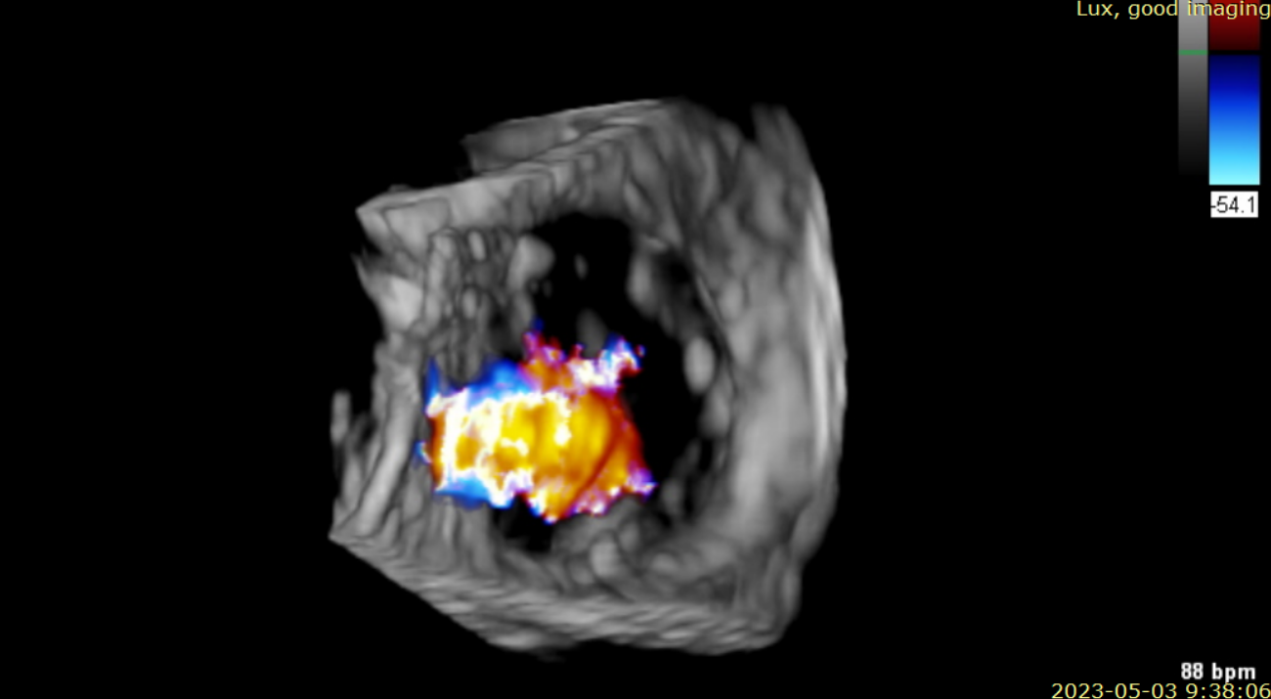

術(shù)后超聲提示無瓣周漏

術(shù)后超聲提示僅殘余輕微瓣周漏

術(shù)后Azeem Latib教授對LuX-Valve Plus經(jīng)血管三尖瓣置換系統(tǒng)的器械性能和治療效果大為稱贊,并且認(rèn)為LuX-Valve Plus的手術(shù)體驗(yàn)非常好。從治療效果來看,術(shù)后即刻超聲顯示三尖瓣反流幾乎完全消失,血流動力學(xué)改善顯著,患者恢復(fù)快。在面對復(fù)雜解剖結(jié)構(gòu)、超聲影像質(zhì)量不佳、有起搏導(dǎo)線干擾時(shí),Lux-Valve Plus也體現(xiàn)了極強(qiáng)的適應(yīng)性。Thomas Modine教授參與了術(shù)中指導(dǎo),他同樣再次肯定了LuX-Valve Plus術(shù)中操作的便捷性,認(rèn)為LuX-Valve Plus容錯(cuò)率高,對術(shù)中影像的依賴小,并表達(dá)了后期希望可以更多地應(yīng)用LuX-Valve Plus三尖瓣置換系統(tǒng)于臨床實(shí)踐,讓更多的三尖瓣重度反流患者盡早獲益,改善預(yù)后。